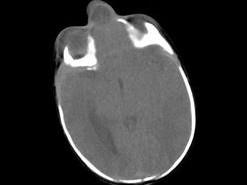

问题 出生两天的男婴,鼻根部眉间正中有一肿块,CT检查如图,请选择最可能的诊断 ( )

选项 A、鼻息肉 B、鼻咽癌 C、脑膨出 D、硬膜外囊肿 E、蛛网膜囊肿

答案 C